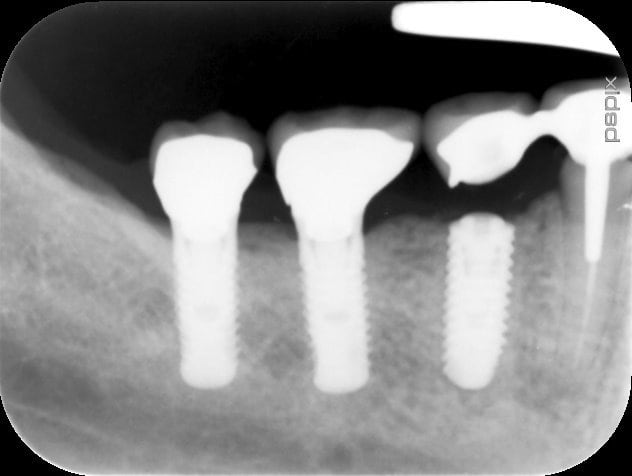

tiens pour m'amuser j'ai revu la patient aujourd'hui et au bout de 9 ans on a perdu la 45 bon on lui a remis un petit clou l'année dernière et refait sa 45 sur implant (le fait de les avoir fait par trois m'a permis une temporisation facile...)

la réhabilitation a maintenant dix ans d vie en bouche les implants sont toujours la mais pas la 45

Bruxogirl suite bbcfre - Eugenol